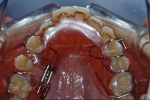

ホーレータイプ

多くの場合後戻りしやすいのは前歯部なので、ここを重点的に押さえて臼歯部はフリーにしてあるタイプをホーレータイプのリテーナーと言います。ホーレータイプもベッグタイプも構造的には歯を動かす装置が付いていない床矯正装置と言えます。